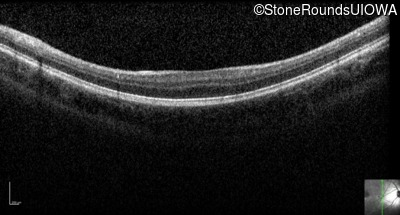

Optical Coherence Tomography - Right - 20/63 -2 sc

Exemplar / OCT Stack

OCT Stack